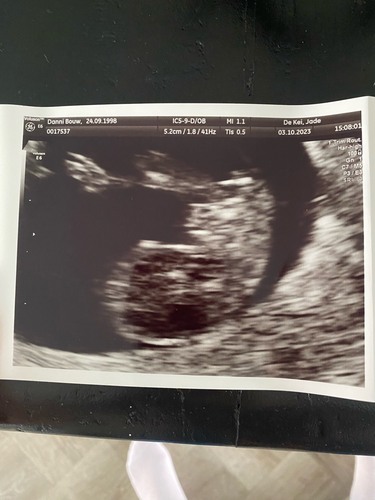

Hee wat grappig, ik zit ook bij babyimage! Wat maakt dat jij op dit termijn ...

We waren daar voor een pretecho, met mijn ouders. Om mijn zorgen een beetje weg te nemen een tussentijdse geboekt. Normaal zit ik hier niet. Wel jammer, want vind het een mooie praktijk! Vind jij dat ook? Hoe ver Ben jij?

Ik inmiddels bijna 12 weken, dus het schiet hier flink op! Kan bijna niet geloven dat ik 12 weken schrijf 😍